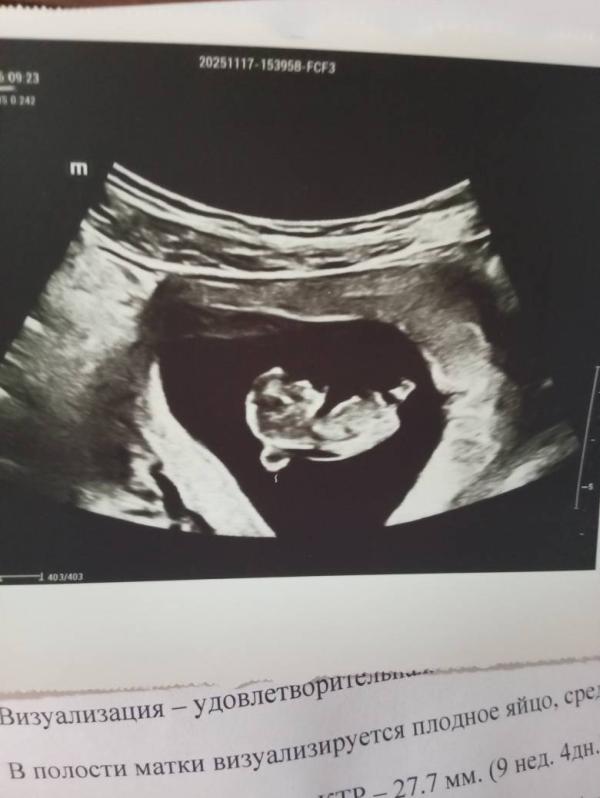

Наша история беременности: всё отлично и прекрасно растем

У нас все отлично!) опасность обошла стороной)))

Мы прекрасно растём и двигаемся! 💗🥰